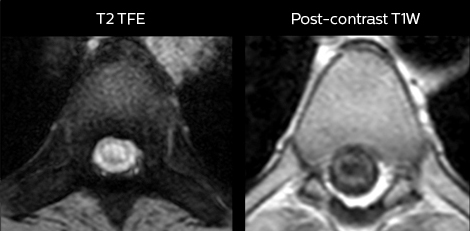

To minimize the time taken to perform scans, rapid MRI examination protocols (ExamCards) were developed, shortening the total scanning time to even less than 10 minutes in some exams. Techniques like mDIXON (modified DIXON) are used for robust capturing of fat-free MRI images in a hectic ED environment.

“We use mDIXON TSE extensively in our spine imaging in the emergency room,” says Dr. Karis. “It’s particularly nice in that it is very robust with regard to susceptibility type of problems that would come up with traditional spectral fat-saturated images; these problems are essentially eliminated with the mDIXON technique. In our ED environment it’s really nice to have the fat-free imaging that goes along with the mDIXON technique.